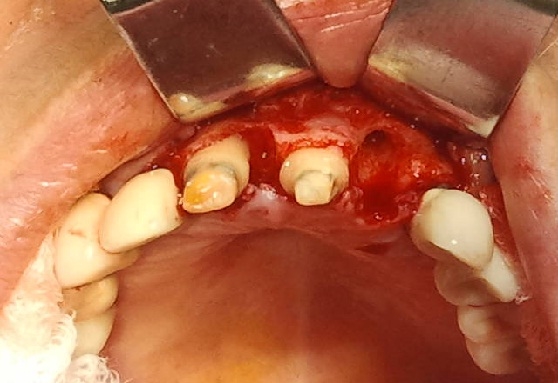

Bogata w płytki i leukocyty fibryna jest stosowana w regeneracji tkanek od ponad 15 lat. Pozytywny wpływ PRF (platelet-rich fibrin) na regenerację tkanek miękkich jest niewątpliwy, bezsporny i częściowo udowodniony w badaniach klinicznych i analizach biochemicznych. Wpływ PRF na regenerację tkanki kostnej jest obserwowany klinicznie, ale nadal niedostatecznie poznany jest mechanizm tego zjawiska.

Platelet- and leukocyte-rich-fibrin has been used in regeneration of tissue for more than 15 years. The positive influence of PRF on the regeneration of soft tissue is undoubtedly, without question and partially proven in clinical studies and biochemical analysis. Influence of PRF on regeneration of bone tissue is observed clinically but the mechanism of this phenomenon is still not sufficiently known.